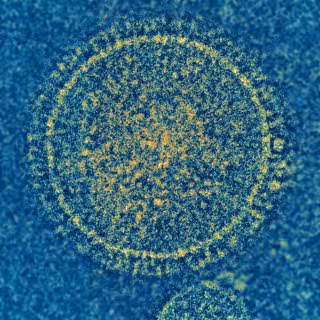

El virus sincitial respiratorio (VSR) es el responsable de una enfermedad común de la infancia. No hay vacuna para prevenir la infección por VRS.

El virus sincitial respiratorio (VSR) es el responsable de una enfermedad común de la infancia. No hay vacuna para prevenir la infección por VRS. - NIAID - Archivo